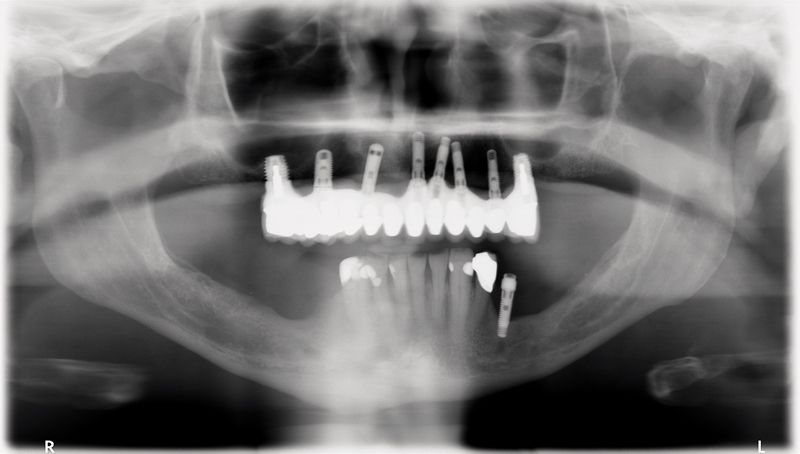

11 The restoration and remaining crowns were returned to the dentist (Fig. 13). The BellaTek Framework was seated intraorally and secured with manufacturer-specific abutment screws. These were tightened to the appropriate torque per each manufacturer’s instructions. The implant-supported crowns corresponding to tooth Nos. 5, 8, and 12 were cemented with NX3 Cement (Kerr) while tooth Nos. 3, 4, 6, 7, 9, 10, 11, 13 and 14 were cemented with temporary cement so the screws could be accessed for removal, if necessary (Fig. 14). A panoramic radiograph was taken (Fig. 15).

Fig. 15?Panoramic radiograph of the definitive restoration.

This patient was successfully treated with a CAD/CAM (BellaTek) framework that has been shown to fit accurately on multiple implant connections. Although the patient had received implant from three manufacturers and several were non-optimally placed, the case was recovered successfully by combining conventional prosthodontic principles with advanced implant restorative technologies.